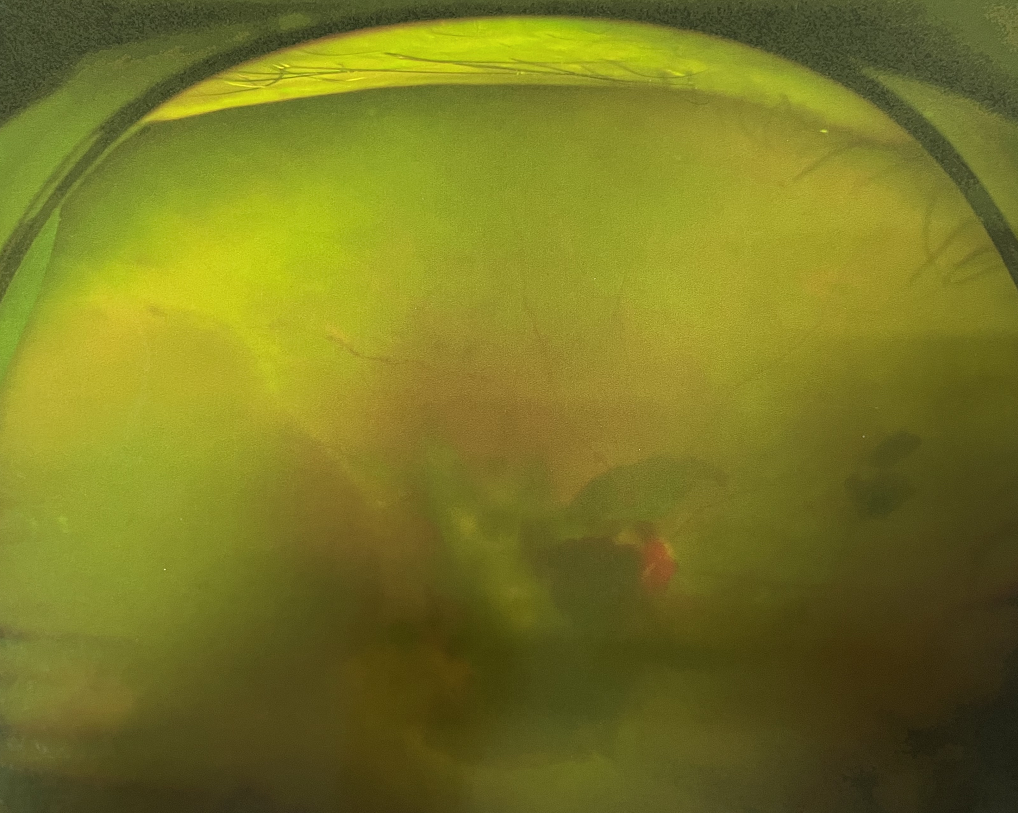

眼底出血是指眼內(nèi)視網(wǎng)膜出血,或玻璃體內(nèi)出血。眼底位于眼睛深處,所以這類出血只靠肉眼是看不到的,早期可能不紅、不痛、不癢,需通過專業(yè)的眼底檢查才可看到,往往短期內(nèi)就可造成視力驟降甚至失明!

同樣的,眼底出血也是一種癥狀,而非病種。誘發(fā)眼底出血的原因很多,常見的有全身性血管病和血液病、視網(wǎng)膜血管異常、機械性阻塞、炎癥性疾病或免疫復合物侵犯血管壁等。